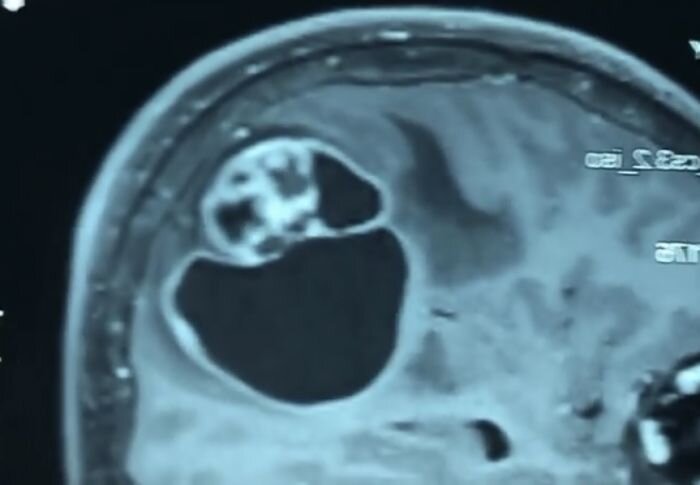

Hemangioblastomas – diagnosis and treatment in Kiev